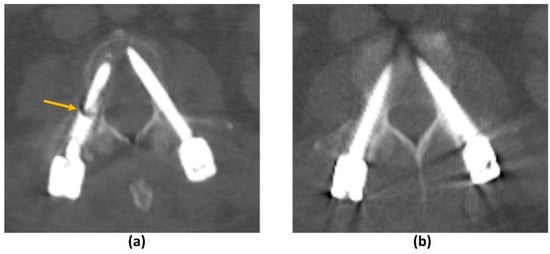

- Katsura, M.; Sato, J.; Akahane, M.; Kunimatsu, A.; Abe, O. Current and Novel Techniques for Metal Artifact Reduction at CT: Practical Guide for Radiologists. Radiographics 2018, 38, 450–461. [Google Scholar] [CrossRef] [PubMed]

- Huber, F.A.; Sprengel, K.; Müller, L.; Graf, L.C.; Osterhoff, G.; Guggenberger, R. Comparison of different CT metal artifact reduction strategies for standard titanium and carbon-fiber reinforced polymer implants in sheep cadavers. BMC Med. Imaging 2021, 21, 29. [Google Scholar] [CrossRef]

- Andersson, K.M.; Nowik, P.; Persliden, J.; Thunberg, P.; Norrman, E. Metal artefact reduction in CT imaging of hip prostheses—An evaluation of commercial techniques provided by four vendors. Br. J. Radiol. 2015, 88, 20140473. [Google Scholar] [CrossRef] [PubMed]

- Li, H.; Noel, C.; Chen, H.; Harold Li, H.; Low, D.; Moore, K.; Klahr, P.; Michalski, J.; Gay, H.A.; Thorstad, W.; et al. Clinical evaluation of a commercial orthopedic metal artifact reduction tool for CT simulations in radiation therapy. Med. Phys. 2012, 39, 7507–7517. [Google Scholar] [CrossRef]

- Axente, M.; Paidi, A.; Von Eyben, R.; Zeng, C.; Bani-Hashemi, A.; Krauss, A.; Hristov, D. Clinical evaluation of the iterative metal artifact reduction algorithm for CT simulation in radiotherapy. Med. Phys. 2015, 42, 1170–1183. [Google Scholar] [CrossRef]

- Puvanasunthararajah, S.; Fontanarosa, D.; Wille, M.L.; Camps, S.M. The application of metal artifact reduction methods on computed tomography scans for radiotherapy applications: A literature review. J. Appl. Clin. Med. Phys. 2021, 22, 198–223. [Google Scholar] [CrossRef]